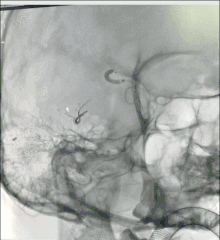

血管造影显示大脑中动脉下干数分支参与畸形团供血,异常引流静脉向右侧乙状窦引流。

经讨论,大家一致认为,经动脉入路无法完全栓塞该畸形团,决定采用动静脉联合入路的方式栓塞畸形团。在右侧股动脉和右侧股静脉处各放置一根6F导管鞘。

将navien导引导管经股静脉导管鞘超选到右侧乙状窦。用Traxcess14导丝将阿波罗导管经navien超选到回流静脉畸形团处。

将Scepter C 4*15球囊经颈内动脉超选到大脑中动脉颞支(畸形团主要供血动脉),充盈球囊,阻断动脉端畸形团血流。

经静脉及动脉依次注射ONYX18约4ml,注胶时,球囊的阻断起到了关键作用(高压锅技术)。

静脉端持续打胶。

术后造影见AVM已经完全栓塞。